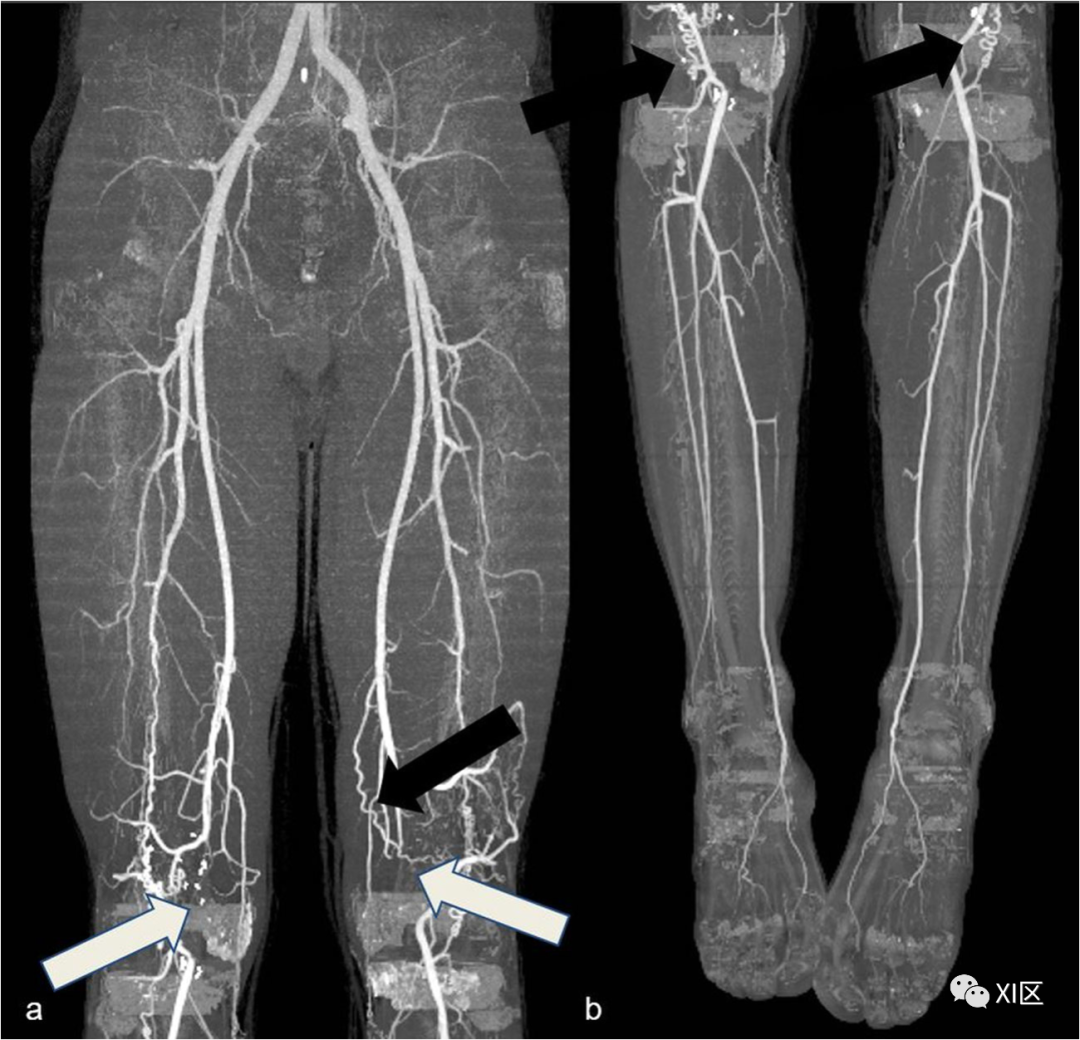

图7 腘窝夹闭综合征。45岁男性,双侧腘窝卡压综合征。大腿(a)和腿(b)冠状位MIP重建。双侧腘动脉未显影(白色箭头),侧枝血管(黑色箭头)清晰可见。

腘动脉夹闭(图7)是指腘动脉与腓肠肌的异常关系,导致动脉受压和跛行,尤其是年轻患者。高达67%的病例存在双侧累及。在临床检查中,主要表现为远端脉搏正常,脚处于中立位置,当脚被迫背屈或跖屈时脉搏消失。